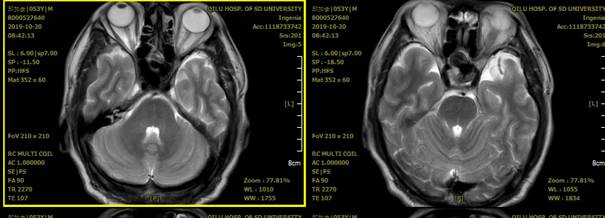

- 查体影像:MRI检查示“蝶窦内异常信号;考虑颈内动脉动脉瘤可能”。

左侧颈内动脉C3段大动脉瘤,大小约23*11mm,瘤颈长度7.4mm,载瘤动脉远端直径约3.8mm,近端直径约4.2mm。